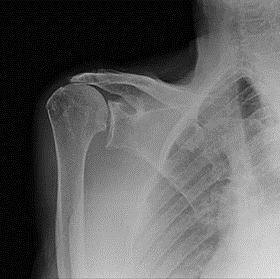

Initieel wordt geprobeerd de pijn weg te krijgen met medicatie, inspuitingen en kinesitherapie. Het krachtsverlies blijft er altijd bestaan vermits er geen nieuwe aanhechting komt van de verloren pezen.

Indien dit niet lukt en de patiënt blijft met veel pijn zitten is er de optie om de schouder te vervangen met een kunstgewricht die de twee problemen, die er zijn, oplost.

Het pijnprobleem wordt opgelost door nieuwe gewrichtsoppervlaktes, het krachtsverlies en pseudo verlamming door een veranderde mechaniek in de schouder met verleggen van rotatiepunten en krachtsarmen.